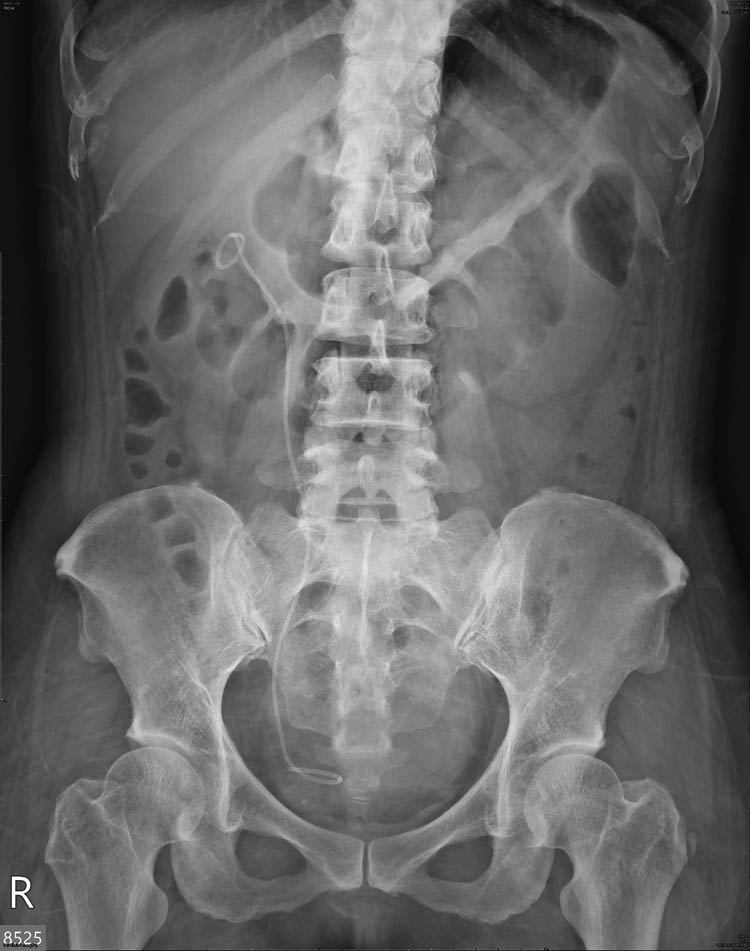

Postoperative KUB revealed the disappearance of the radiopaque lesion in the right renal shadow (Figure 6). The patient’s symptoms also improved and neither flank pain nor gross hematuria was noted during follow-up. Three weeks after the procedure, the double J stent was removed without complications.

Postoperative KUB showed disappearance of the radiopaque lesion at right kidney area. Right double J ureteral stent were in situ.